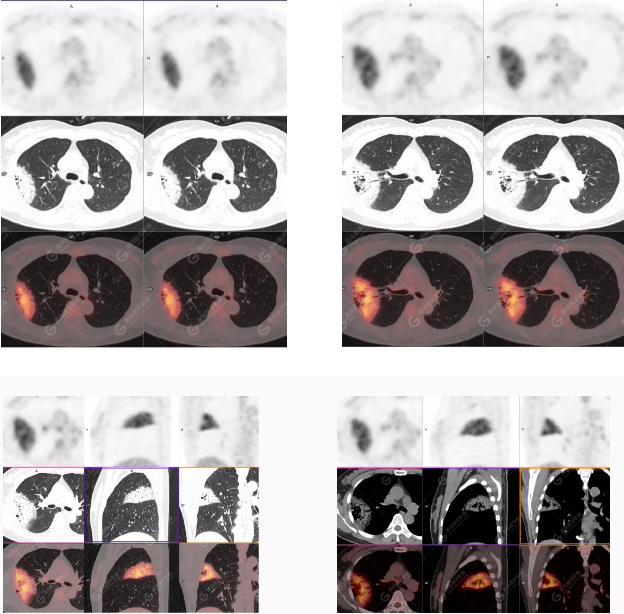

PET/CT影像圖

右肺上葉斑片狀高密度影,部分實變,邊界清楚,未跨葉間裂;內(nèi)空氣支氣管征、蟲蝕樣空洞、周圍暈征;放射性攝取增高,SUVmax=4.1。

右肺上葉后段胸膜下片塊狀高代謝病灶,考慮為肺淋巴瘤,請結(jié)合臨床病理。病理報告